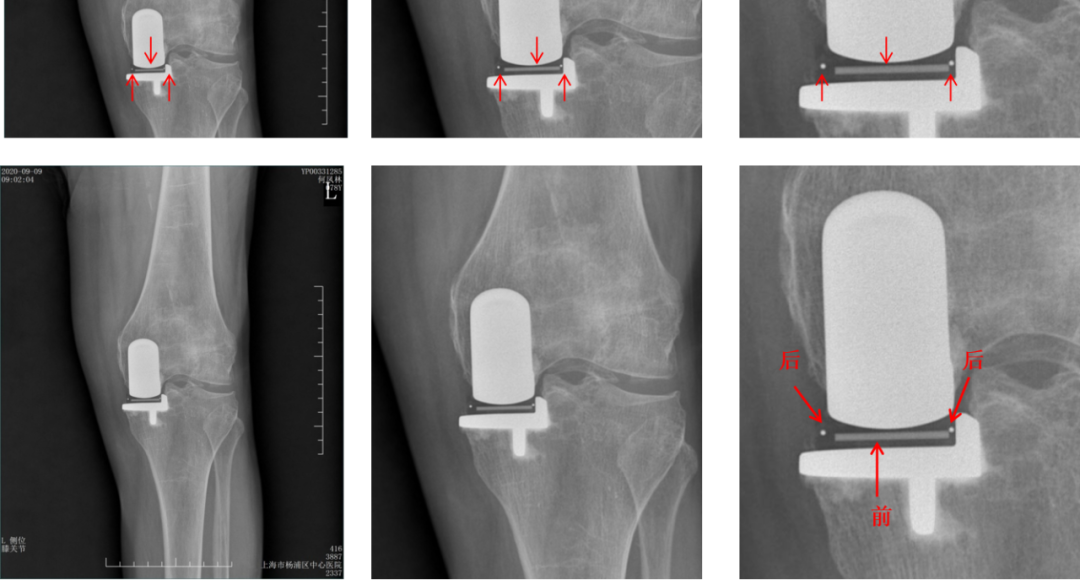

Bearing 中立位( X-ray正位)

Bearing 内旋( X-ray正位)

Bearing 外旋( X-ray正位)

辨认bearing内的标识( X-ray正位)

bearing 内的标识:点和线段 “ .—. ” 线段显示为“—”在前;点显示为“.”在后